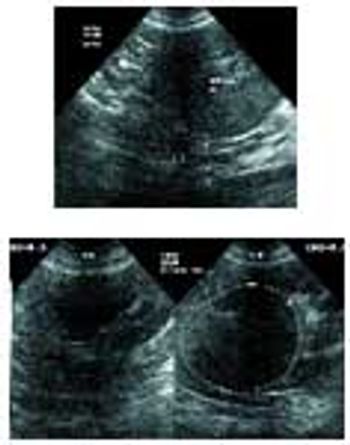

Signalment: Canine, Greyhound, 2.5 years old, female spayed, 65 lbs. Clinical history: The dog has a persistent urinary tract problem ? hematuria for at least one year according to the owner. The dog improves with antibiotics, but once finished, hematuria starts again. Therapy has included Clavamox.